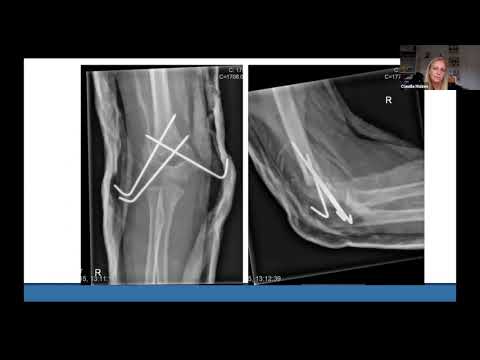

Supracondylar Humerus Fractures: Basic Simple Steps for pinning/K wire

SUPRACONDYLAR FRACTURES Pinning configurations - Merits and problems - Anirban Chatterji IFICS 2016